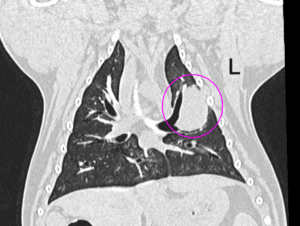

症例1 フレンチ・ブルドッグ 8歳 避妊メス

<主訴>

慢性的な後肢ふらつきがあり、胸腰部MRIを依頼しようとしたら麻酔前検査で胸部に腫瘤形成が疑われた。

<CT所見>

肺野・左前葉前部に2〜3cmの腫瘤性病変

肺野に転移を疑う所見なし

リンパ節にも転移を疑う所見なし